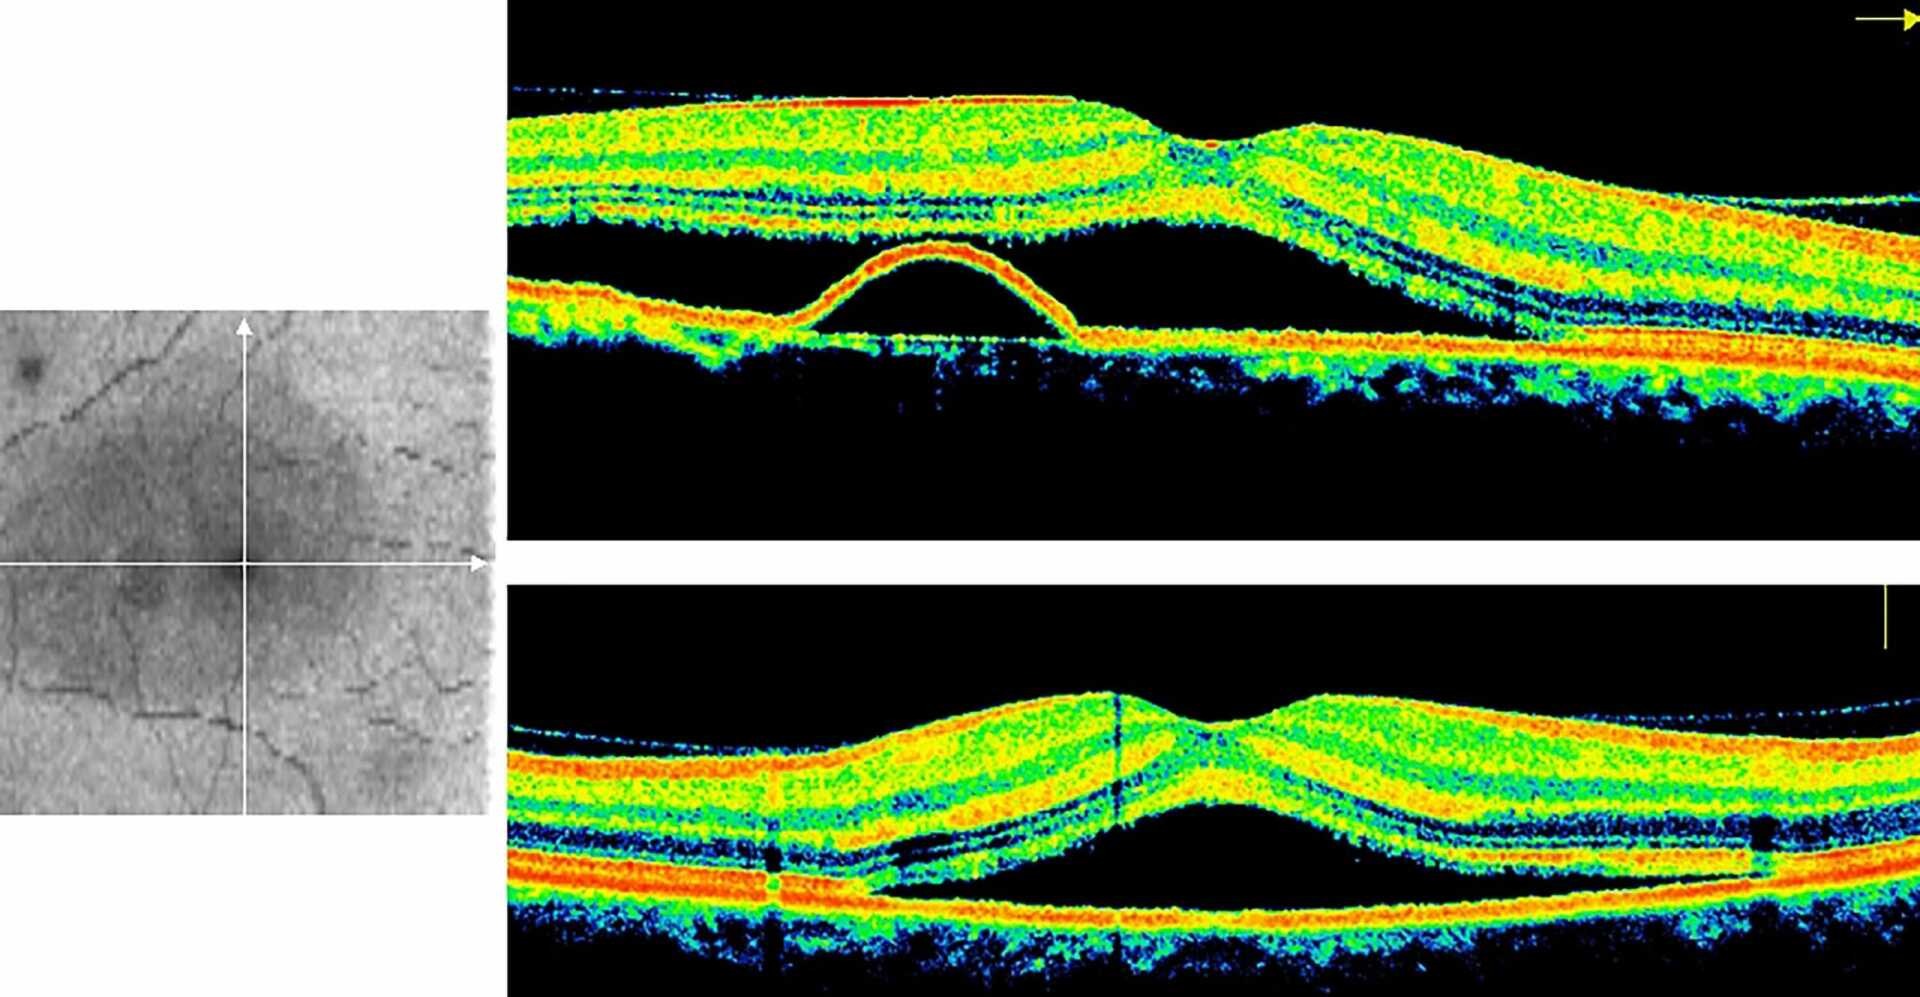

- Elle est définit par la présence de liquide sous la rétine (DSR ou décollement sous-rétinien) traversant l’épithélium pigmentaire au niveau d’un « point de fuite » au-dessus d’une choroïde épaissie et pathologique.

- Les examens sont le fond d’œil, l'OCT maculaire, l’angio-OCT et l’angiographie rétinienne.